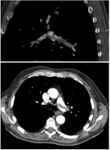

| Chest spiral CT scan with radiocontrast agent showing multiple filling defects both at the bifurcation ("saddle" pulmonary embolism) and in the pulmonary arteries. | |

On CT scan, pulmonary emboli can be classified according to level along the arterial tree.

التصوير الطبقي المحوسب

التصوير الطبقي المحوسب للرئة والمصحوب باستخدام الصبغة المشعة في الوريد أصبح واسع الانتشار والاستخدام في تشخيص المرضى المشتبه بإصابتهم بالانصمام الرئوي، لهذا النوع من التصوير حساسية تبلغ 83% ودقة نوعية تصل إلى 96%.[24].[25]